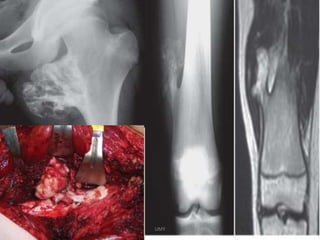

DHRUV 8/M ABC

Rx-curettage+ Chron os grafting

UMY